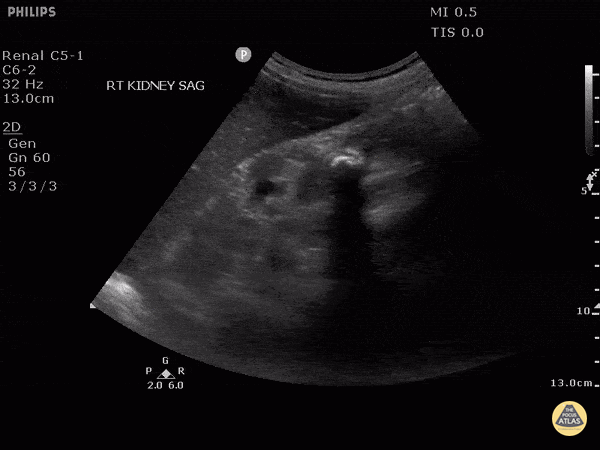

This clip demonstrates medullary nephrocalcinosis. Note the increased echogenicity of the renal pyramids due to calcium deposition. Image courtesy of Robert Jones DO, FACEP @RJonesSonoEM Director, Emergency Ultrasound; MetroHealth Medical Center; Professor, Case Western Reserve Medical School, Cleveland, OH View his original post here